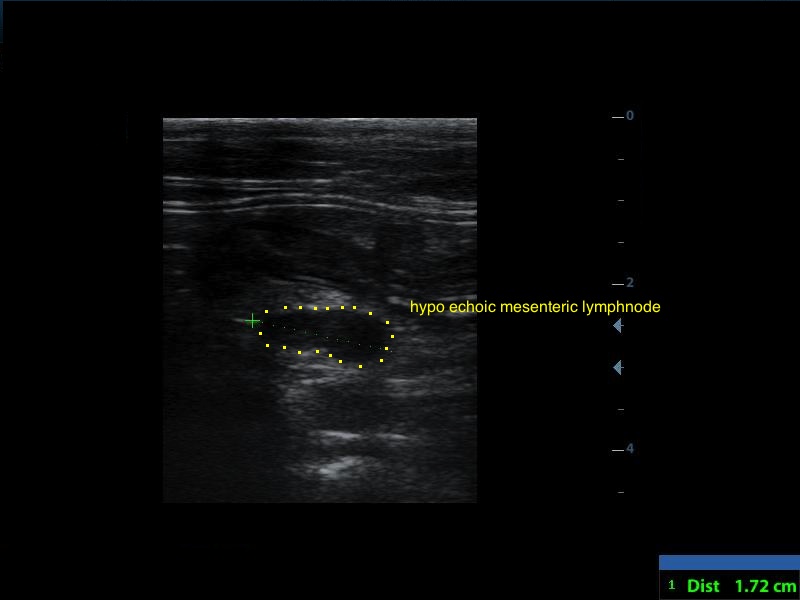

The spleen was increased in size with a diffuse parenchymal hyperechogenicity. A small section of the small intestine was enlarged with loss of its normal wall layers (pic1). The surrounding fat tissue was also hyperechoic. An enlarged regional mesenteric lymphnode was noted with diffuse hypoechogenicity. A Fine Needle Aspiration was performed in order to collect cytology speciments from the spleen and the intestinal lesions. The diagnose was alimentary tract lymphoma.

Image series, through the normal anatomy, to the lesion of the small intestine, in a perpendicular view.